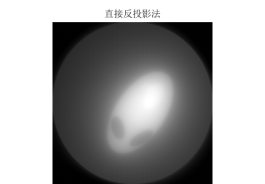

图 9

图 10

图 11

由滤波公式与原来灰度像素矩阵每一列进行卷积,得到了消除边缘失锐的灰度像素矩阵再用原本未滤波的模型进行图形重建运算,程序见附录程序四,结果以及效果如下:

图 14

图 15

图 16